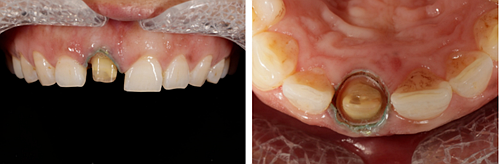

患者右上前牙因外傷冠修復(fù)體脫落來我院找口腔修復(fù)科金小婷醫(yī)師治療。經(jīng)檢查,患者剩余牙體組織少,經(jīng)溝通確認后,進行上前牙全瓷冠修復(fù)。

△術(shù)前比色